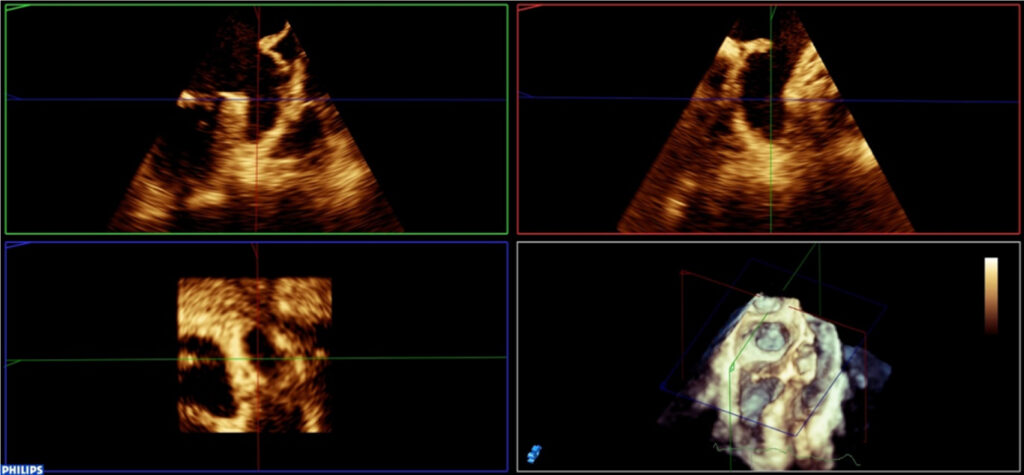

O apêndice atrial esquerdo (AAE) é uma extensão do átrio esquerdo (AE) e apresenta uma estrutura anatômica complexa e propriedades fisiopatológicas únicas. O AAE funciona como uma câmara de descompressão durante a sístole ventricular esquerda e em condições de pressão atrial esquerda elevada. Apesar de anteriormente ter sido considerado uma porção relativamente insignificante da anatomia cardíaca, o AAE vem se destacando como uma estrutura importante envolvida na gênese da formação de trombos e eventos tromboembólicos. Mais recentemente, com o desenvolvimento dos dispositivos de fechamento percutâneo, a avaliação da morfologia do AAE tornou-se cada vez mais importante.

O presente artigo visa descrever a anatomia e morfologia do AAE, os parâmetros para avaliação da sua função, os desafios no diagnóstico de trombos e as principais modalidades de imagens com ênfase no ecocardiograma transesofágico.